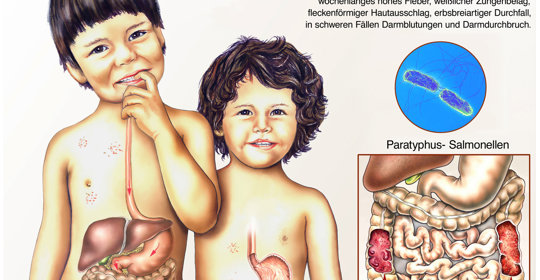

兒童腹痛:症狀、檢查及治療,關心兒童腹部不適

兒童遺糞症:症狀、檢查及治療,瞭解兒童排洩問題